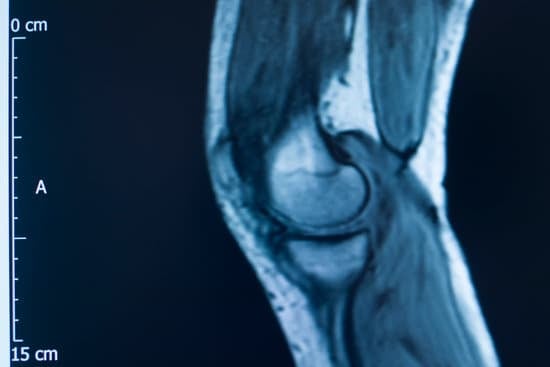

MRI: 손상의 정도와 정확한 부위를 평가하는 데 사용됩니다.